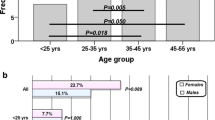

Nineteen patients (63.3%) had evidence of decreased neuronal function on PET-CT. Only 1 patient had bilateral brain involvement while the remaining 18 had left brain involvement. Five (26.3%) out of the 19 patients had single lobe involvement while 14 (73.7%) had multiple lobes involved (11 had two, 3 had three lobes involved). The temporal lobe was most commonly involved (n = 18, 94.7%), followed by the parietal (n = 14, 73.7%) and frontal lobes (n = 3, 15.8%). The occipital lobe was not involved in any patient.

Risk factors for decreased neuronal function

There was no statistically significant correlation between the evidence of decreased neuronal function on PET-CT and any of age, gender, transfusion history, total hemoglobin level, or platelet count. The median serum ferritin level was higher in patients with PET-CT abnormality than those without (1,215 vs. 861.5 μg/l), although the association did not reach statistical significance (P = 0.053). Moreover, the median LIC was significantly higher in patients with evidence of decreased neuronal activity than those without (16.3 vs. 3.4 mg Fe/g dw, P = 0.003). A logistic regression model was also performed to estimate the probability of abnormality on PET-CT using LIC as an independent variable (Fig. 1). The model was significant (P < 0.001) and had a predictive value of 76.7%. On ROC curve analysis, a LIC cutoff of 15 mg Fe/g dw was the best predictor of decreased neuronal function on PET-CT with an area under the curve of 0.828 ± 0.075 (95% confidence interval 0.681–0.975, P = 0.003), a sensitivity of 52.6%, and a specificity of 100%.

Among the group of 30 patients, 18 (60%) had evidence of silent infarcts on brain MRI, all in the white matter [12]. A total of 11 patients (36.7%) had evidence of brain abnormality on both MRI and PET-CT while 26 patients (86.7%) had evidence of brain abnormality on either MRI or PET-CT (Table 2). The concordance rates between brain MRI and PET-CT were 36.7% for the detection of abnormality (Kappa 0.056, P = 0.757); 23.3% for the detection of multiple abnormalities (Kappa 0.062, P = 0.732); 3.3% for the detection of bilateral brain abnormality (Kappa 0.086, P = 0.245); and 6.7% (Kappa 0.036, P = 0.713), 10% (Kappa 0.164, P = 0.338), 3.3% (Kappa 0.045, P = 0.406), and 0% (Kappa N/A, P = N/A) for the detection of frontal, parietal, temporal, or occipital abnormalities, respectively (Fig. 2).